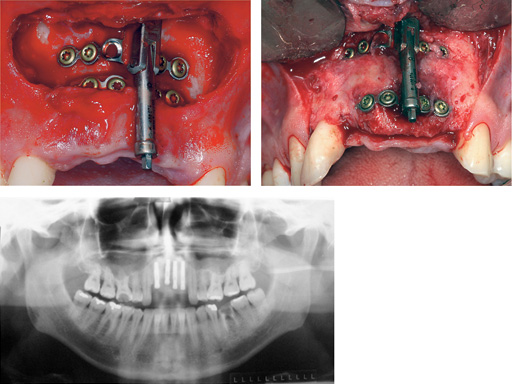

Distraction of a fibula flap in the mandibular body after tumor resection. The additional pin provides stabilization.